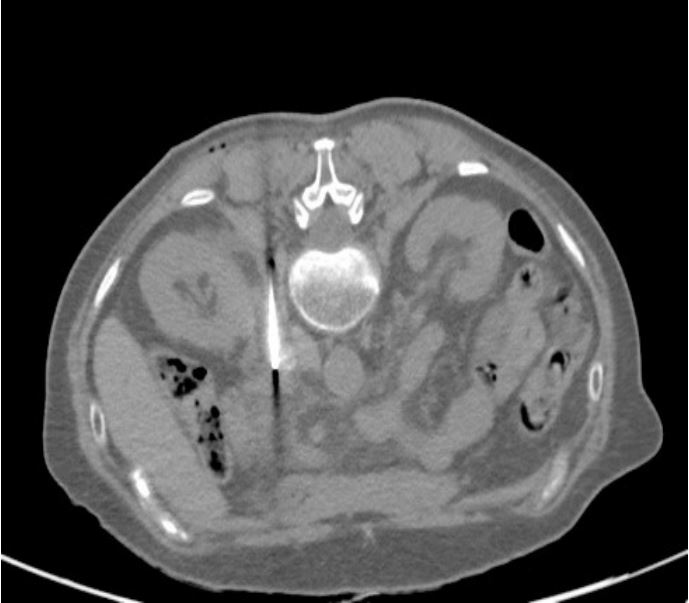

Figure 2: CT scan during the cryoablation procedure. The needle tip is placed within the lesion.